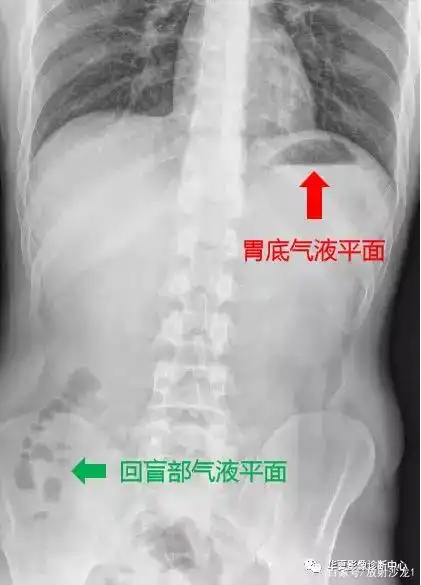

理论联系实践,带你全面剖析肠梗阻x线表现